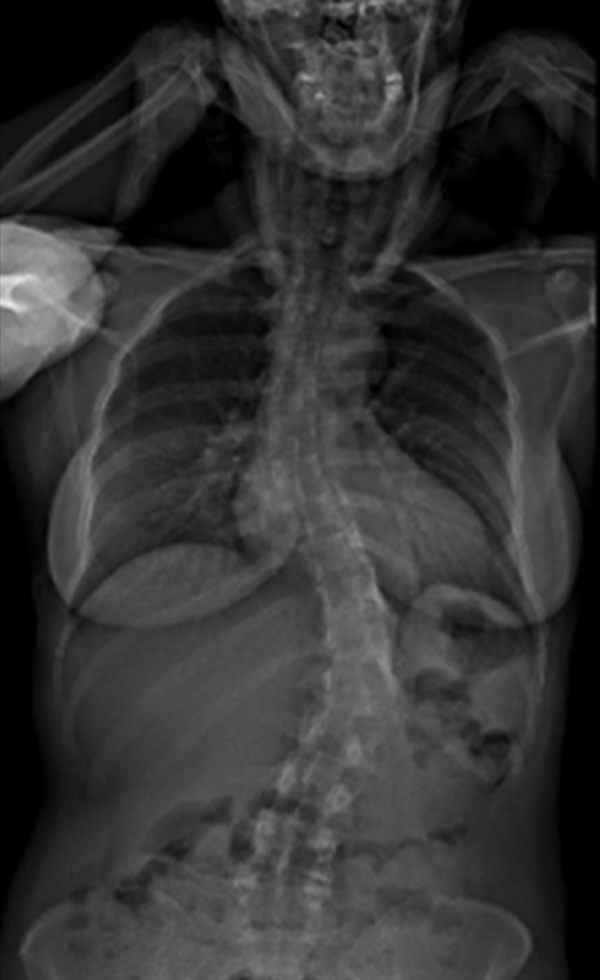

Gallery : Before - After